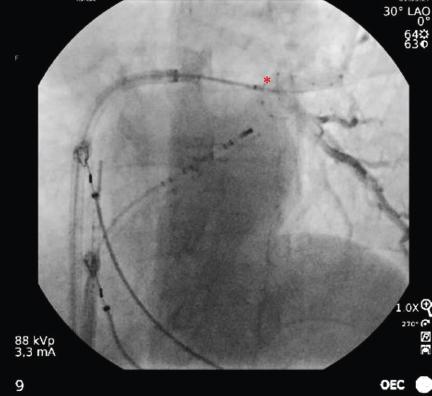

Figure 3